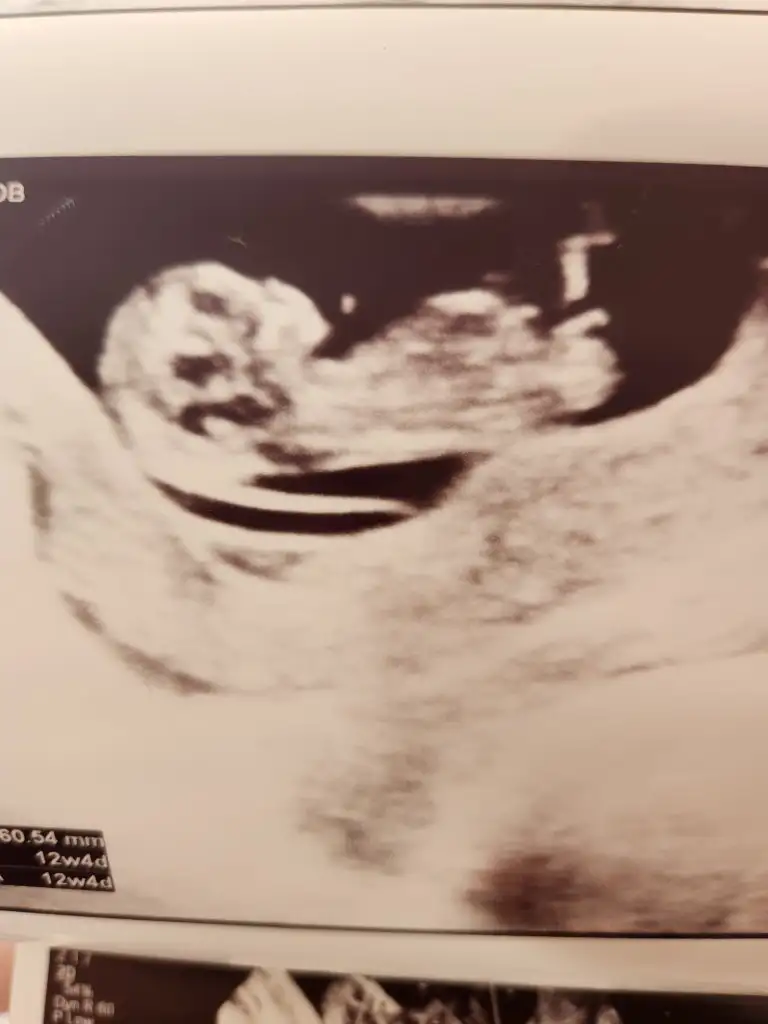

12 haftada benimkini demisti doktorum seninkide erkek benceBugün dayanamadım gittim doktora bayramdan sonrayı bekleyemicektim. En son 9 haftada gördüm şimdi 12 yiz :) Çok şükür duydum kalp atışını :) Aç olduğum için bir türlü pozisyon değiştirmedi boyunu ölçemedi doktor sadece ufak hareketler yaptı :) Cumartesi tekrar gideceğim. Ve bakarken doktor içimden erkek galiba bu dedim aynısını eşimde demiş